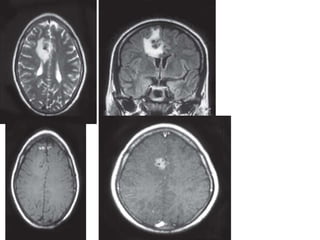

T1W sagittal (A) and T2W axial (B) MR images showing

multiple lesions having a hypointense center on T1 and hyperintense

center on T2W images with perilesional edema. The collagenous capsule

of the lesions is iso to slightly hyperintense on T1 and hypointense on

T2W images. Mass effect on the ipsilateral ventricular system with

dilatation of the contralateral temporal horn is seen — multiple brain

abscesses